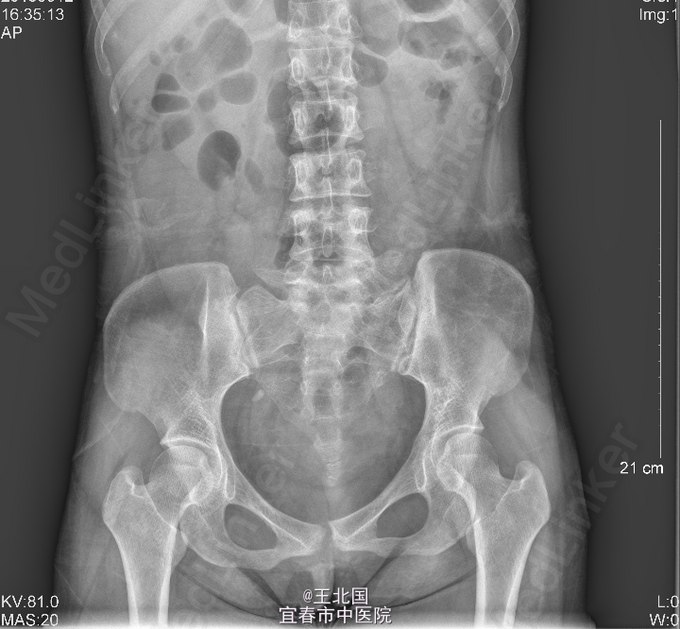

3、查体:右肾区叩痛可疑阳性,余未见异常 4、辅助检查:双肾输尿管膀胱彩超:右侧输尿管中段结石并右肾积液;左侧输尿管未见扩张;左肾超声检查未见明显异常;膀胱超声检查未见明显异常。腹平片及静脉泌尿系造影均提示:右侧输尿管下段结石,右肾及右输尿管中重度扩张、积液,右肾功能减退低

5、诊断:输尿管结石 6、处理:入院后完善相关检查:腹平片及静脉泌尿系造影均提示:右侧输尿管下段结石,右肾及右输尿管中重度扩张、积液,右肾功能减退低。行“右侧输尿管镜碎石取石术”,术中取尽结石后,见右侧输尿管迂曲,进镜及进导丝困难,后留置4F输尿管支架管一条。术后行泌尿道逆行造影,见右侧输尿管迂曲,造影剂通过正常。患者术后恢复可,顺利出院